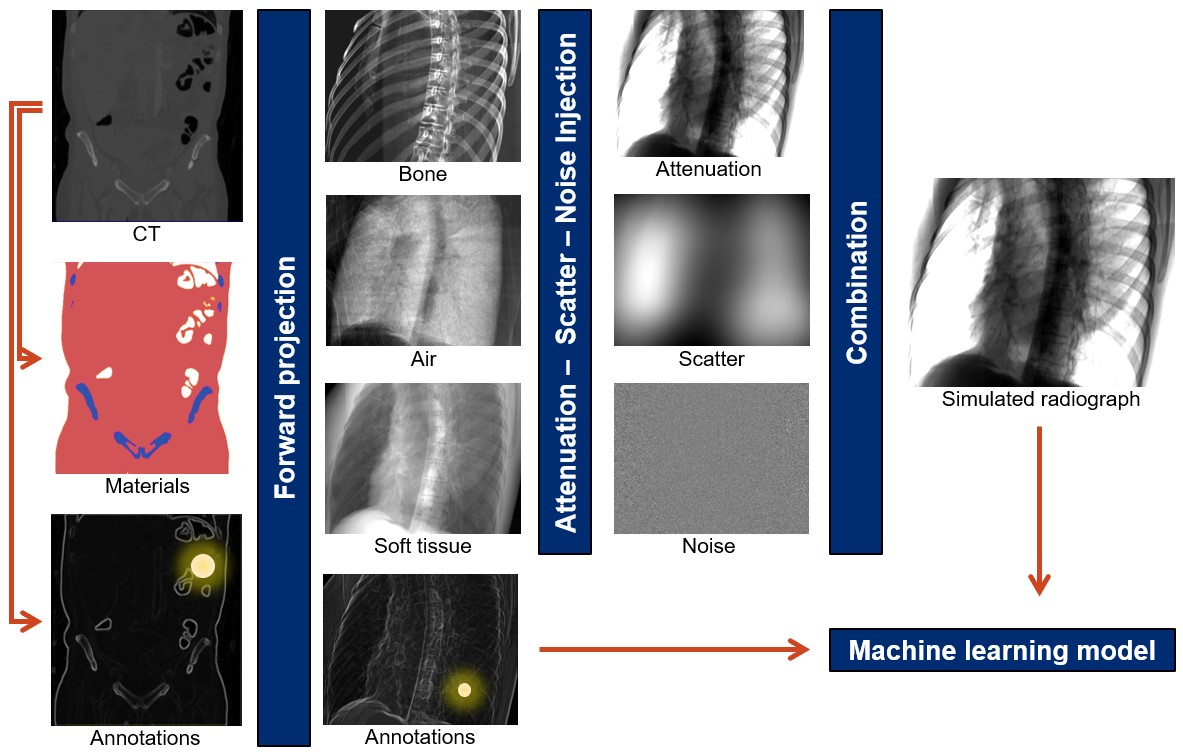

First steps in addressing the data problem have been taken, serving as a stepping stone for the transformative technology that is intelligent imaging. While large scale acquisition of highly structured data is tractable for some interventional applications, particularly ultrasound [61, 62], most other approaches rely on synthetic data generation from physical models of the scene. This paradigm is attractive because all quantities of interest are precisely known by design, however, if simulation is performed naïvely, AI models trained on synthetic data will not generalize to clinically acquired images because of the large domain mismatch paired with poor generalizability of today’s models [57]. Three complementary ways have recently been shown to mitigate this problem. First, if clinically acquired data is available in addition to the well annotated synthetic data, style transfer algorithms can be trained that alter the appearance of real data to close the domain gap, as shown for ophthalmic surgical microscopy [63, 64]. Using such enhanced simulated data for training of more complex tasks has been applied successfully to endoscopy [65] and X-ray imaging [66]. Second, if too little clinical data is available, learning a style transfer algorithm is impossible. In these cases, a powerful alternative is increasing the realism of synthetically generated images in a model-based approach. Doing so requires accurate models of all physical principles that govern image formation, however, approximations are usually required to reduce simulation time to acceptable levels. Realistic simulation works well for X-ray-based modalities as illustrated in Figure 2) and demonstrated in [67, 57]. It has also been proposed in endoscopic imaging [68]. However, the level of required realism likely depends on the application and learning target, since it has been shown that even less realistic simulations could be adequate, e. g., in some ultrasound applications [69]. The aforementioned approaches aim at reproducing real data appearance which is very complicated in practice. If closely matching real data appearance is found to be impossible, domain randomization can be used to improve the robustness of the trained model to partially unseen data. Rather than perfectly matching real data characteristics, the goal of domain randomization is to generate multiple versions of the same sample with all but the important characteristics randomized. When training AI algorithms on such datasets, the models are assumed to become robust to these types of domain changes. Domain randomization can be seen as image formation-based data augmentation and has recently been applied to X-ray imaging [70] as well as colonoscopy [68], where achieving realistic image appearance is very complicated due to fine texture and specular reflectance of the tissue. It is worth mentioning that all the above techniques for synthetic data usage are similar in that AI algorithms never process real data during training. This characteristic is associated with a notable drop in performance when applied to real data due to residual domain mismatch. Consequently, assessing algorithmic performance only on a synthetic test set will severely overestimate the AI models accuracy during deployment and quantitative experiments on clinical data are required. Ultimately, training the AI directly on real data is preferable, highlighting the need for further research on un- and self-supervised learning to leverage large quantities of unlabeled data.